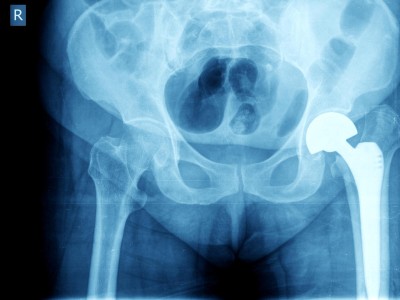

Hüftprothesen aus dem 3D-Drucker?

Personalisierte Endoprothesen sind eine vielversprechende Entwicklung in der Orthopädie, aber sie stehen auch vor erheblichen regulatorischen, mechanischen und finanziellen Herausforderungen. Die größte Herausforderung stellt bei uns die Kostenerstattung dar.

Kann eine Hüft-TEP über 30 Jahre lang halten?

Eine aktuelle Studie des Heidelberger Universitätsklinikums untersuchte insgesamt 348 Hüft-Totalendoprothesen (TEP), die zwischen 1985 und 1989 implantiert wurden. Zu welchen Ergebnissen kam die Studie?

Berliner Dom/© Photocreo Bednarek / Stock.adobe.com, Ärzteteam führt Hüftoperation durch/© ATRPhoto / stock.adobe.com (Symbolbild mit Fotomodell), Ein älteres Pärchen fährt Fahrrad/© Halfpoint / stock.adobe.com (Symbolbild mit Fotomodellen), Frau greift an ihre Ferse/© Satjawat / stock.adobe.com (Symbolbild mit Fotomodell), Distale Radiusfraktur/© Joel bubble ben / stock.adobe.com, Frau bei Knochenmineraldichte-Messung/© gelmold / stock.adobe.com (Symbolbild mit Fotomodell), Viele Ärzte versorgen einen Patienten/© Monkey Business / Stock.adobe.com (Symbolbild mit Fotomodellen), Röntgenbild Hüftprothese/© oceandigital / Fotolia, Transmurale Ruptur der Supraspinatussehne/© Wahal N et al. / all rights reserved Springer Medizin Verlag GmbH, Bluttransfusion im Rettungshubschrauber/© [M] Chalabala / Stock.adobe.com, Physiotherapeutin behandelt Fußbeschwerden/© aldomurillo / Getty Images / iStock (Symbolbild mit Fotomodellen), Narbe nach Kniegelenkersatz-Operation/© GalinaSt / stock.adobe.com (Symbolbild mit Fotomodell), DGOU Logo/© Deutsche Gesellschaft für Orthopädie und Unfallchirurgie, Berlin/© eyetronic / Stock.adobe.com, Hallux valgus/© Springer Medizin, Modell des Kniegelenks/© edwardolive / Stock.adobe.com (Symbolbild), Lumbale Spinalkanalstenose/© Birkenmaier C & Fuetsch M / all rights reserved Springer Medizin Verlag GmbH, Anteriore Schulterluxation im Röntgenbild/© Spagna G et al. / all rights reserved Springer Medizin Verlag GmbH, Chirurginnen und Chirurgen im OP/© Tobilander / stock.adobe.com (Symbolbild mit Fotomodellen), Schulterarthroskopie/© Issara / stock.adobe.com (Symbolbild mit Fotomodellen), Elektronenmikroskopisches Bild eines Biofilms an einer Titanoberfläche (Vergr. 1500:1)/© Holinka J, Windhager R doi.org/10.1007/s00132-016-3247-8 unter CC-BY 4.0, Primäre Hüftgelenkendoprothetik nach Azetabulumfraktur/© Hofmann GO et al. / Springer Medizin Verlag 2008, Osteosynthese einer distalen Radiusfraktur /© Mathias Ernert, Ärztin erklärt einem Patienten das Hüftgelenk/© Daisy Daisy / Stock.adobe.com (Symbolbild mit Fotomodell), Periprothetische Femurfraktur/© Springer Medizin, Vorderes Kreuzband/© Springer Verlag GmbH, MRT-Sequenz vom Knie/© Springer Medizin, Schweres Thoraxtrauma/© Christoph Nau · Birte Weber · Ingo Marzi / all rights reserved Springer Medizin Verlag GmbH, Ruptur der Rotatorenmanschette/© Springer Medizin, Wirbelkörper/© CreVis2 / Getty Images / iStock, Hallux valgus/© masanyanka / stock.adobe.com, Rotatorenmanschette/© Springer Verlag GmbH, Röntgenbild eines künstlichen Hüftgelenks/© Nicolas Larento / Fotolia, Minimalinvasive AC-Gelenk-Operation/© Springer Medizin, Rettungsassistenten liefern Notfallpatientin auf einer Trage in ein Krankenhaus ein/© Stephan Jansen / dpa / picture alliance, Idiopathische Skoliose/© Springer Medizin Verlag GmbH, Bandscheibenvorfall der LWS schematisch /© psdesign1 / Fotolia, Frau fasst sich an die Wade/© KSR / Fotolia , Liposarkom/© Davorin Wagner / Chirurgie im Bild, Narbe nach Kniegelenkersatz/© Miriam Dörr / Fotolia (Symbolbild mit Fotomodell), Weiße Tabletten im Blister/© bogo-service / Fotolia